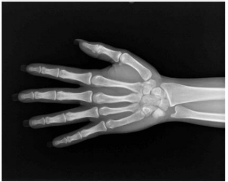

Em um paciente com lesão no punho, a radiografia permite

observar fraturas da porção distal do rádio ou da ulna, fraturas

isoladas dos estiloides radiais e ulnar, assim como fraturas dos

ossos do carpo individuais. Podem ser igualmente demonstrados

nesses exames alguns processos patológicos, tais como

osteomielite ou artrite.

Sobre a análise dessa estrutura em INCIDÊNCIA AP (PA): PUNHO a partir de exame radiológico, assinale a alternativa correta.